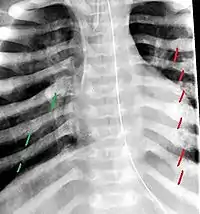

The material factual allegations of the amended complaint are as follows. Plaintiff was born on May 14, 1970. On repeated occasions during the first year of her life she was severely beaten by her mother and the latter's common law husband, one Reyes. On April 26, 1971, when the plaintiff was eleven months old, her mother took her to the San Jose Hospital for examination, diagnosis, and treatment. The attending physician was defendant Dr. Flood, acting on his own behalf and as agent of the defendant San Jose Hospital. At the time, the plaintiff was suffering from a comminuted spiral fracture of the right tibia and fibula, which gave the appearance of having been caused by a twisting force. Plaintiff's mother had no explanation for this injury. Plaintiff had bruises over her entire body. In addition, she had a non-depressed linear skull fracture which was then in the process of healing. Plaintiff demonstrated fear and apprehension when approached. Inasmuch as all plaintiff's injuries gave the appearance of having been intentionally inflicted by other persons, she exhibited the medical condition known as the battered child syndrome.

The complaint avers that as a proximate result of the foregoing negligence plaintiff was released from the San Jose Hospital without proper diagnosis and treatment of her battered child syndrome, and was returned to the custody of her mother and Reyes who resumed physically abusing her until she sustained traumatic blows to her right eye and back, puncture wounds over her left lower leg and across her back, severe bites on her face, and second and third degree burns on her left hand.

On this appeal plaintiff has expressly abandoned her claim of punitive damages. It is alleged that proper diagnosis of plaintiff's condition would have included taking X-rays of her entire skeletal structure, and that such procedure would have revealed the fracture of her skull. Defendants negligently failed to take such X-rays, and thereby negligently failed to diagnose her true condition. It is further alleged that proper medical treatment of plaintiff's battered child syndrome would have included reporting her injuries to local law enforcement authorities or juvenile probation department. Such a report would have resulted in an investigation by the concerned agencies, followed by a placement of plaintiff in protective custody until her safety was assured. Defendants negligently failed to make such report. The complaint avers that as a proximate result of the foregoing negligence plaintiff was released from the San Jose Hospital without proper diagnosis and treatment of her battered child syndrome, and was returned to the custody of her mother and Reyes who resumed physically abusing her until she sustained traumatic blows to her right eye and back, puncture wounds over her left lower leg and across her back, severe bites on her face, and second and third degree burns on her left hand.